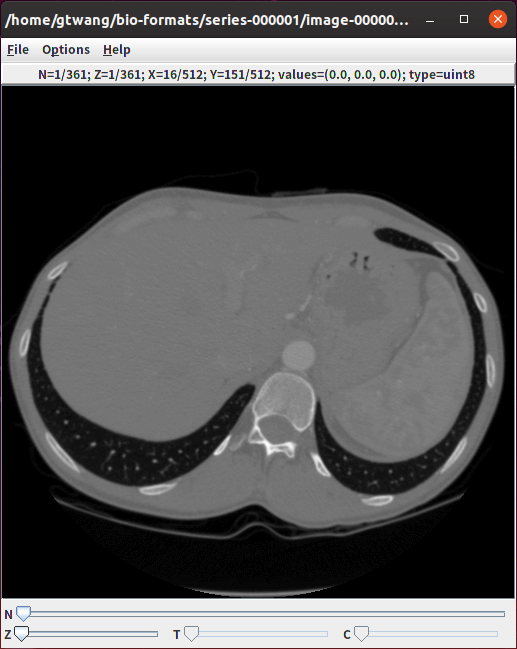

大部分的生醫影像在觀看時,都需要調整影像的色階,否則會看不出來實際的內容,若要自動調整影像色階,可以加上 -autoscale 參數:

# 自動調整影像色階

showinf -autoscale image.dcm

在 ImageJ 中以 Bio-Formats 匯入影像時,會先出現這個選項視窗,裡面有各種匯入選項可以調整。

這就是以 Bio-Formats 將 DICOM 影像匯入 ImageJ 的樣子。